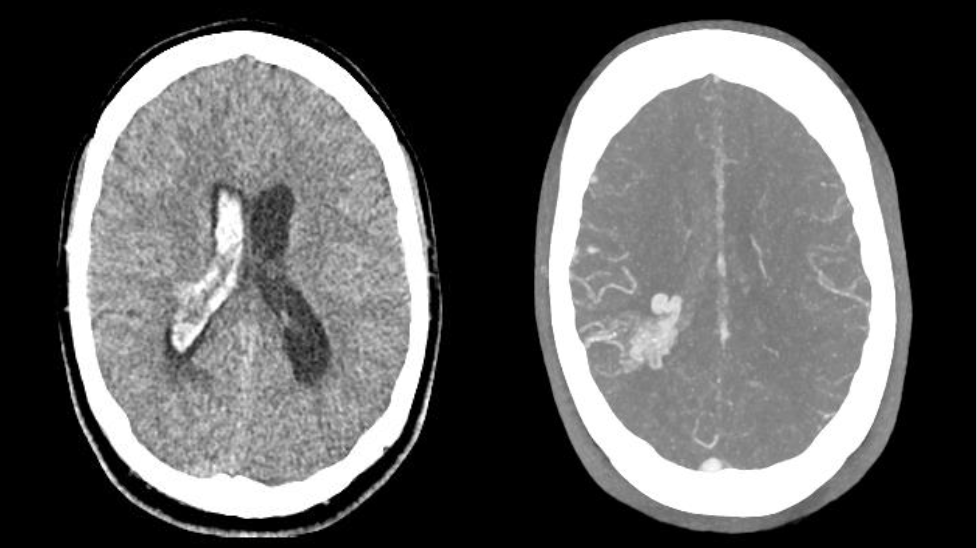

Tratamiento combinado de malformación arteriovenosa con sangrado reciente